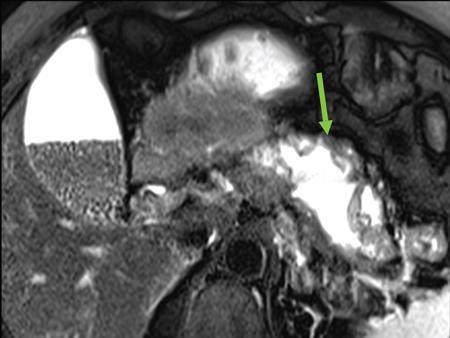

Anirudh Kohli Acute pancreatitis is one of the most dreaded diseases to afflict mankind, in view of its high morbidity and mortality. The single most important factor in reducing the morbidity and mortality of this condition over the last many years has been the role of computed tomography (CT). The incidence of acute pancreatitis is rising especially due to an increasing incidence of gallstones, obesity, as well as an ageing population. Pancreatitis occurs due to a chain of events triggered by a temporary/permanent pancreatic duct obstruction. This leads to activation and release of pancreatic enzymes into pancreatic interstitium and peripancreatic tissues leading to severe auto digestion and necrosis of pancreas and adjacent tissues. Systemically there is release of inflammatory mediators known as cytokines. Tumour necrosis factor is a cytokine which is toxic to acinar cells. These cytokines activate and intensify the inflammatory cascade that may ultimately culminate in multiorgan failure. Clinically severe acute pancreatitis is characterized by two phases, an early phase and a late phase. The early phase is dominated by the systemic effects of release of inflammatory mediators such as cytokines – termed as systemic inflammatory response syndrome (SIRS). Usually there is associated variable multiorgan dysfunction/failure. This phase lasts for a week. When the multiorgan failure lasts 2 days it is termed as mild, multiorgan failure lasting more than 48 hours is considered severe. There is no correlation between the clinical severity of pancreatitis and morphological changes in this early stage. In view of this CT scan is not of much utility during this phase, unless complications are suspected. The later phase is dominated by effects of local complications due to pancreatic/peripancreatic necrosis. Mortality follows this biphasic pattern in early weeks from the systemic effects of multiorgan failure and in later weeks due to local effects, for example infection of necrotic pancreatic/peripancreatic tissues superimposed by organ failure. The Clinical diagnosis of acute pancreatitis requires two of the following three features: If the first two findings are present without any significant SIRS then CT is not required. Acute pancreatitis is a complex disease with a wide variation in the presentation and outcome, ranging from asymptomatic with only biochemical alterations to a fatal outcome. In fact acute pancreatitis is a dynamic disease with continuously evolving appearances on imaging. There are two distinct forms of acute pancreatitis – interstitial oedematous pancreatitis and acute necrotising pancreatitis. Interstitial oedematous pancreatitis is a condition where there is only mild swelling of the pancreas with loss of normal lobulations and a diffuse decrease in attenuation of the pancreas. There may be heterogeneity of the pancreatic parenchyma due to varying degrees of interstitial oedema. This form of pancreatitis runs a mild course and rarely progresses to acute necrotising pancreatitis with its associated complications. In a third of these cases the pancreas may reveal no abnormality on a CT scan. The inflammatory changes may be restricted to the pancreas or extend into the peripancreatic regions. The inflammation in the peripancreatic regions manifests as acute pancreatic effusions. If there is peripancreatic fat necrosis with an oedematous pancreatic gland it is termed as acute necrotising pancreatitis (Figs. 9.17.1–9.17.2). Acute pancreatic fluid collections are enzyme-rich pancreatic juice collections seen in about 40% of patients with acute pancreatitis. The fluid collections occur due to exudation of pancreatic juices into the interstitium of the pancreas and subsequently leakage into the surrounding tissue spaces. These fluid collections are localized only by the anatomic space in which they collect. As the exudative process continues, the parietal peritoneum overlying the pancreas may be disrupted with the inflammatory fluid entering the lesser sac. From the lesser sac the fluid can enter the peritoneal cavity via the foramen of Winslow or by dissecting the peritoneum along the anterior surface of the lesser sac. Posterior extension of the fluid collection in the anterior pararenal space may occur into a potential space between the laminae of the posterior pararenal fascia. Rarely there may be involvement of the perirenal and posterior pararenal spaces. Other pathways of dissection are along the gastrohepatic, gastrosplenic and gastrocolic ligaments. Fluid may dissect along the root of the mesentery into the transverse mesocolon. Collections may extend around the caecum, ascending colon, descending colon and into the lumbar, pelvic and inguinal regions. Large fluid collections may dissect superiorly into the mediastinum or pericardial space. The quantity of fluid in these effusions is variable and can range from a small amount to large quantities (Fig. 9.17.3). Of these collections, 50% resolve spontaneously; the remainder may evolve after 4–6 weeks into pseudocysts. As the collections age, they tend to get localized and walled off, often developing an enhancing wall. A collection should be termed a pseudocyst only when a definite capsule develops and the collection has been static for at least 4–6 weeks. The risk of complications such as rupture, infection and haemorrhage increases with the age of the collection. Large collections of fluid are usually associated with a lesser degree of pancreatic necrosis as compared to extensive pancreatic necrosis associated with a lesser amount of fluid collection. Acute necrotising pancreatitis is a fulminant form of pancreatitis in which there is necrosis of the pancreas, that is nonviable pancreatic tissue. A contrast-enhanced CT is essential as it is the ideal means to demonstrate necrosis as well as to determine the extent of necrosis. These areas of nonviable pancreatic tissue do not enhance as compared to viable pancreatic tissue, which demonstrate significant enhancement. The extent of pancreatic necrosis has been found to correlate extremely well with the extent of necrosis found at surgery. The size, location and extent of pancreatic necrosis are very variable. These areas may be diffuse or focal, small in size to complete glandular involvement. These necrotic areas have a very important bearing on the course of pancreatitis, as they are liable to undergo secondary infection and form pancreatic sepsis. In addition, the more extensive the pancreatic necrosis the greater is the morbidity and mortality. Patients with no pancreatic necrosis have been found to have a 0% mortality and a 6% complication rate, whereas patients with pancreatic necrosis have a 23% mortality rate and an 82% complication rate. A variety of laboratory tests are available to detect pancreatic necrosis, such as a rise in the serum methemalbumin, quantitative estimation of C-reactive protein and urinary trypsinogen-activated peptide. CECT is still the most accurate modality to detect pancreatic necrosis. Pancreatic necrosis may be seen in the pancreas only, peripancreatic tissues also or only in the peripancreatic region. Isolated peripancreatic necrosis occurs due to disruption of the peripheral ductules with extravasation of activated pancreatic enzymes, may be seen in up to 20% of patients who require operative/interventional management of their necrotising pancreatitis. These patients with only peripancreatic necrosis have a better prognosis. This essentially represents retroperitoneal fatty tissue necrosis appearing as heterogeneous areas of liquid and nonliquid components. Over time necrosis evolves and liquefies as well as the liquid component resorbs. Generally if the liquid component is 2 cm or less it will resorb, while fluid collections 5 cm or more rarely resorb. If pancreatic necrosis is not resorbed it may get walled off or with time or may become infected. Encapsulation occurs between the third and fourth weeks. It is important to differentiate sterile from infected necrosis as sterile necrosis rarely needs surgery, whereas infected necrosis requires long-term antibiotic therapy and/or some kind of imaging/surgical intervention. According to the Atlanta 2012 classification, all areas of pancreatic necrosis are termed as acute necrotic collections. This represents a combination of pancreatic/peripancreatic fat necrosis with peripancreatic effusions. On CT, there is a spectrum of findings – solid, liquid containing debris (these may be nonwalled off/partially walled off). Sonography and MRI have advantages over CT scan in demonstration if the contents are pure liquid such as acute pancreatic effusions or have some nonliquefied components such as acute necrotic collections. Pseudocysts are round or oval encapsulated fluid collections containing only liquefied components. It takes 4 weeks for the granulation tissue to develop. On CT, a pseudocyst appears as a well-defined fluid collection with a thin capsule. The most common location for pseudocysts is the lesser sac, though they may be found anywhere in the mediastinum, abdomen or pelvis as they may dissect along fascial planes, along vessels and through capsules of solid organs. Pseudocysts in the bowel, though reported, are relatively rare, as the bowel wall is a strong barrier to the effect of proteolytic pancreatic enzymes. When the contents of the pseudocyst are heterogeneous or uniformly increased in attenuation, the possibilities of infection or haemorrhage should be considered. Focal areas of increased density within the fluid collection usually indicate haemorrhage. Complicated, enlarging or symptomatic pseudocysts require percutaneous catheter or surgical drainage. Infected pseudocysts are treated by percutaneous drainage. The management of a noninfected pseudocyst is controversial. Surgical treatment is only undertaken when the wall is mature after several weeks. Large pseudocysts greater than 5 cm in size can easily be drained percutaneously using intercostal drainage tube or pigtail catheter or endoscopically via the stomach. The cure rates are reported to be 85% with percutaneous drainage, the drainage period averaging about 20 days (Figs. 9.17.4–9.17.5). Walled off necrosis – as pancreatic/peripancreatic necrosis matures and evolves, an interface develops between necrosis and adjacent fatty tissue and an enhancing thickened wall is seen, resulting in a well-defined fluid collection with necrotic debris and fat necrosis. This is the end stage in the evolution of an acute necrotic collection. It is important to differentiate a pseudocyst from walled off necrosis, as a pseudocyst requires drainage and walled off necrosis requires surgical removal (Figs. 9.17.6–9.17.9). Sepsis is a major complication of pancreatitis and is accompanied by a high incidence of mortality and a prolonged hospital stay. Pancreatic sepsis may occur following secondary infection of pancreatic and/or peripancreatic necrosis, acute pancreatic fluid collections and pseudocysts. The only specific sign to demonstrate sepsis is the presence of gas in a collection. This occurs due to secondary infection by coliform/anaerobic organisms. This sign is unfortunately not common and seen in only one-third of cases. Gas is seen in the fluid collection as very dark well-defined air attenuation bubbles. Occasionally gas may be present due to a gastrointestinal fistula or previous surgery. Fat necrosis is seen in peripancreatic collections. This should not be confused with air bubbles, which are indicative of sepsis. The differentiation is easy to understand by CT, the values of fat ranging between – 20 HU and – 80 HU, and of air being >–300 HU. Also air bubbles have well-defined margins and are homogeneously jet black, whereas fat is nonhomogeneously grey with ill-defined margins. Since the presence of air is seen only in a small percentage of patients with pancreatic sepsis, the only other means to diagnose pancreatic sepsis is by CT-guided aspiration. All sites of fluid collection, parenchymal necrosis and peripancreatic necrosis are subjected to CT-guided aspiration. This is a tedious process and requires a dedicated interventional radiologist as there are often more than 5–6 sites from which it may be necessary to obtain samples. A fresh needle and syringe are used for each site, as it is important to know which site has sepsis and which is sterile. Care is taken not to transgress the large bowel as the colon has a large number of bacteria, and transgressing it could result in colonic bacteria contaminating the CT-guided aspiration sample, with falsepositive results. Further, colonic bacteria may be inoculated into a sterile acute pancreatic fluid collection or necrosis thereby converting a sterile collection into an infected one (Fig. 9.17.10). Complications of the procedure can be pneumothorax if the pleura is transgressed, haemorrhage due to trauma to a vessel, and secondary infection. Pancreatic sepsis is treated by surgical debridement, necrosectomy and drainage through thick tubes. It is crucial from the management point of view to differentiate an abscess from infected necrosis. An abscess may be treated by percutaneous drainage, whereas infected necrosis developing in relatively solid tissue can be treated by surgical debridement alone. Imaging-guided percutaneous drainage is the first step in treating pancreatic sepsis especially patients who are very ill and cannot undergo surgery. Initially pig tail catheters were used but these are notorious to get blocked as the largest bore of a pigtail catheter is 12 F. Pancreatic sepsis contains a large amount of necrotic debris, this blocks the catheters can be cleared by flushing the catheter, but this always raises the possibility of introducing secondary infection. To circumvent this issue large-bore ICD catheters have been introduced. These range from 16 F to 30 F. A safe window is necessary, not transgressing bowel or vasculature. It is quite easy to insert these tubes percutaneously under CT. A bit of initial manipulation and force is required to pierce the abdominal musculature. These large-bore drainage tubes have been very effective unless the infected necrosis is solid with minimal liquefied contents or a safe window for placing an ICD catheter is not available. CT is also invaluable in surgical planning and in the follow-up of postoperative patients to evaluate any fresh collection and also to determine whether the drains are well sited or not (Fig. 9.17.11).